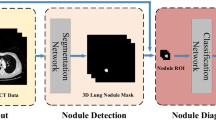

Lung cancer represents one of the most common and lethal types of cancerous pathologies and lung nodules are an early indicator for pulmonary cancer. Hence, a precise and reliable segmentation of lung nodules could enhance early diagnosis and therapy and thus, increase patients’ survival rates. This work proposes a modified 3D-Res2Unet, combining an Unet-style neural network architecture with residual blocks and attention mechanisms. This network was tested on the publicly available LUNA16 CT dataset and achieved on average 91.27 ± 6.49 %. Therefore, the proposed method indicates state-of-the-art performance and could represent an important tool for early diagnosis of lung cancer.

Huang X, Sun W, Tseng TLB, Li C, Qian W. Fast and fully-automated detection and segmentation of pulmonary nodules in thoracic CT scans using deep convolutional neural networks. Computerized Medical Imaging and Graphics. 2019;74:25–36.

Khosravan N, Bagci U. Semi-supervised multi-task learning for lung cancer diagnosis. 2018 40th Annual international conference of the IEEE engineering in medicine and biology society (EMBC). IEEE. 2018:710–3.